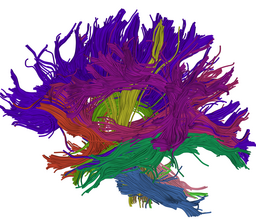

We are developing tools in the 3D Slicer for automatic clustering of tractographic paths through diffusion tensor MRI (DTI) data. By grouping tractographic paths based on shape and location, the white matter architecture may be more clearly visualized, and interesting properties of the clusters (such as for example FA or Westin's linear measure) may be quantified.

Our implementation uses spectral clustering, a method for grouping data using eigenvectors of a data affinity matrix. This image gives an overview of the method. On the left example input tractographic paths are shown (these were created by manually seeding in the 3D Slicer). The center image shows an embedding of the tracts as points in 2D, where the distance between points is related to their shape similarity. This embedding was calculated as an intermediate step during spectral clustering. The image on the right shows the final output in the 3D Slicer, where tractographic paths are colored by cluster membership.

Atlas creation and automatic labeling has been performed in high-quality DTI datasets from Susumu Mori. Images showing example segmentation results are below. Work is underway to apply this atlas to segment additional datasets to define regions of interest that may be used in the study of schizophrenia.

Selected anatomical regions, automatically labeled using the cluster atlas in 3 subjects.